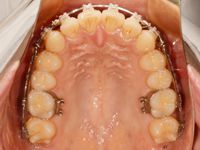

そして、調整後の写真がこちらです![]()

前回と同じように、上顎の奥歯を後ろ方向に動かすために、ゴムをかけたのと、分かりづらいですけど、歯並びの細かい調整のためにワイヤーを調節しています![]()